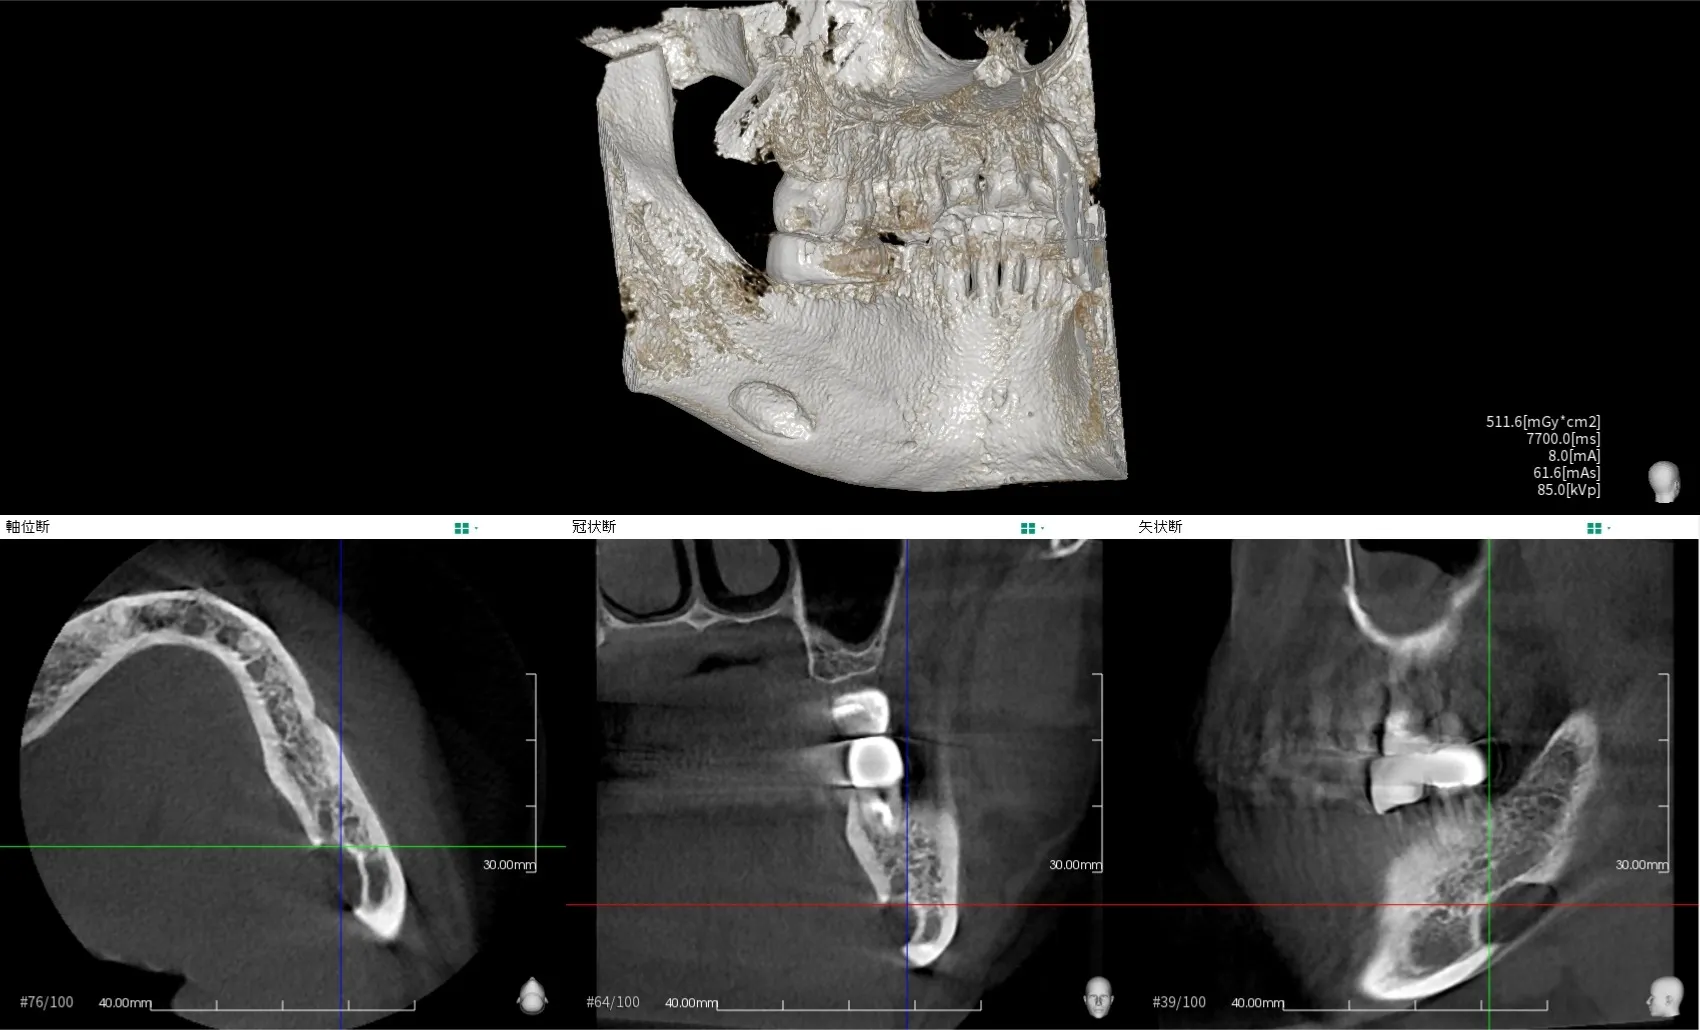

④ 歯科用CT(CBCT)

用途

インプラント治療

親知らずと神経の位置関係

根管の複雑な形態把握

顎骨内病変・嚢胞・腫瘍

外科処置の事前評価

特徴

3D画像で立体的に確認できる

神経・血管・骨の厚みまで正確

「安全な治療計画」に不可欠

被ばく量(目安)

約0.05〜0.2 mSv(撮影範囲により変動)

医科用CTよりはかなり少ない